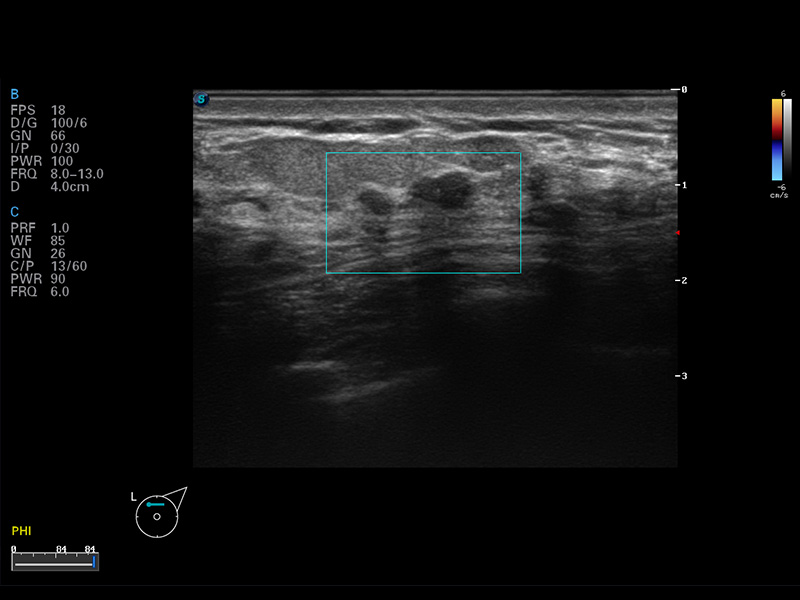

S8 EXP便携式彩色多普勒超声诊断仪是米兰官方网站研发的高端全身应用型便携彩超。高通道的VIS平台融合可视化(Visual)、智能化(Intelligent)和人性化(Smart)的特点,配以米兰官方网站自主研发生产的探头大家族,使您能够快速、准确的获得病人信息,提高工作效率的同时减轻疲劳。

μ-Scan微米成像